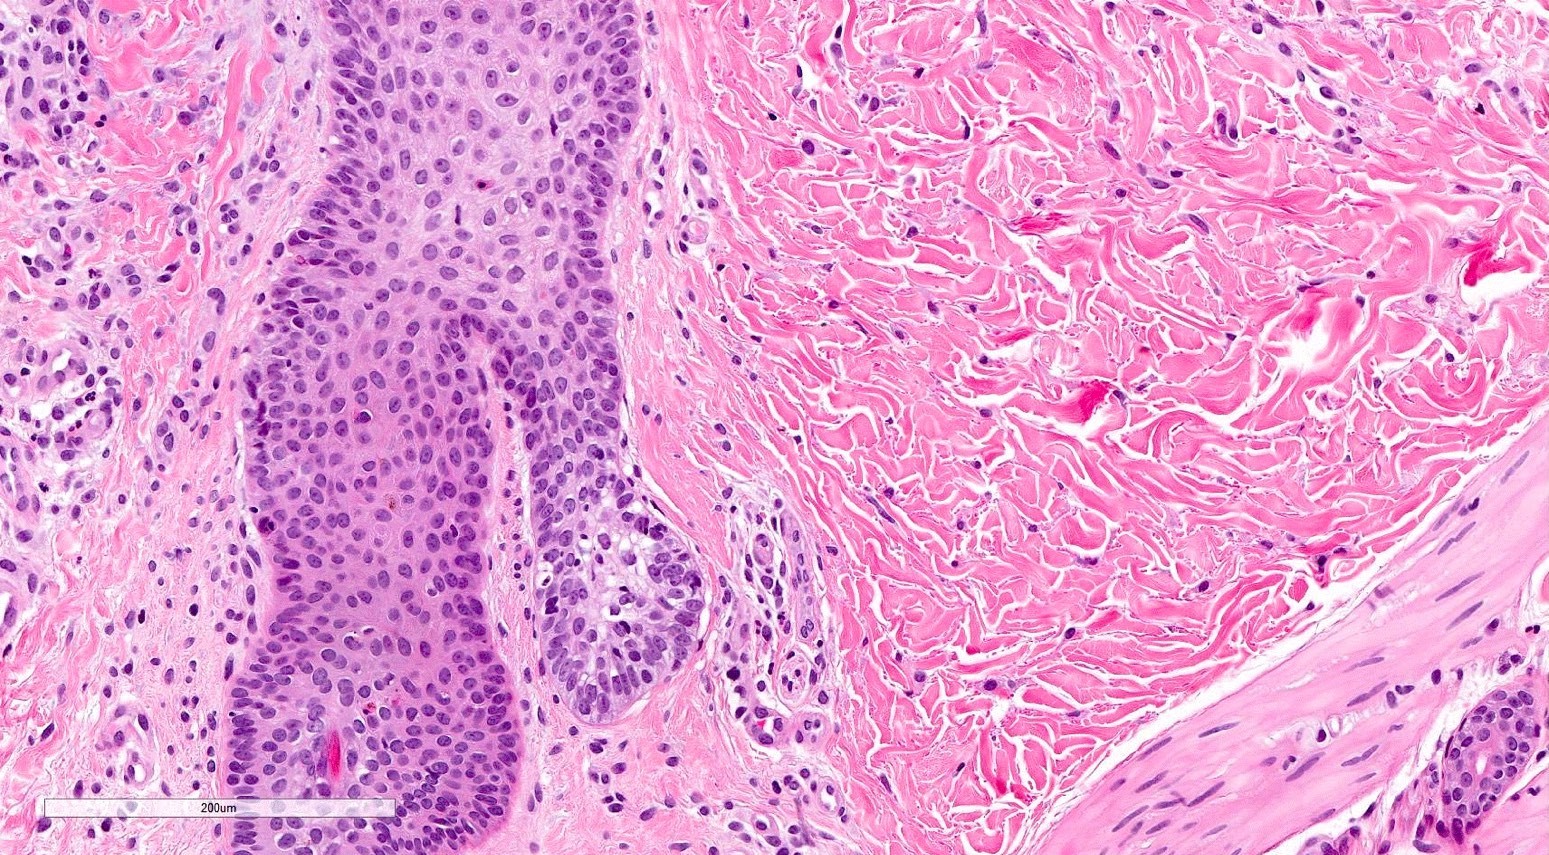

- Acute GVHD (Patterson: Weedon's Skin Pathology, 4th Edition, 2015)

- Mild to moderate superficial perivascular lymphocytic infiltrate with exocytosis of inflammatory cells into the epidermis and basal vacuolation, interface dermatitis

- Scattered, shrunken, eosinophilic keratinocytes with pyknotic nuclei, at all levels of the epidermis; often accompanied by 2 or more lymphocytes, producing the satellite cell necrosis - lymphocyte associated apoptosis

- Occasionally, rare eosinophils can be present; melanin incontinence is prominent in patients with darker skin types

- If severe, subepidermal microvesicles, subepidermal blisters and epidermal necrosis

- Lymphocytic infiltrate in GVHD after solid organ transplantation is usually brisk in comparison to the sparser inflammation following bone marrow transplantation

- Chronic GVHD (Biol Blood Marrow Transplant 2015;21:589, Patterson: Weedon's Skin Pathology, 4th Edition, 2015)

- Chronic lichenoid GVHD

- Acanthosis, orthohyperkeratosis, parakeratosis with hypergranulosis

- Underlying band-like lymphocytic infiltrate with basal layer vacuolization and apoptotic keratinocytes

- Periadnexal inflammation can be present

- May be difficult to distinguish from lichen planus without clinicopathologic correlation; satellite cell necrosis is the most helpful clue in GVHD biopsies to distinguish it from lichen planus

Microscopic (histologic) images

Contributed by Silvija P. Gottesman, M.D. and Ohoud Aljarbou, M.D.